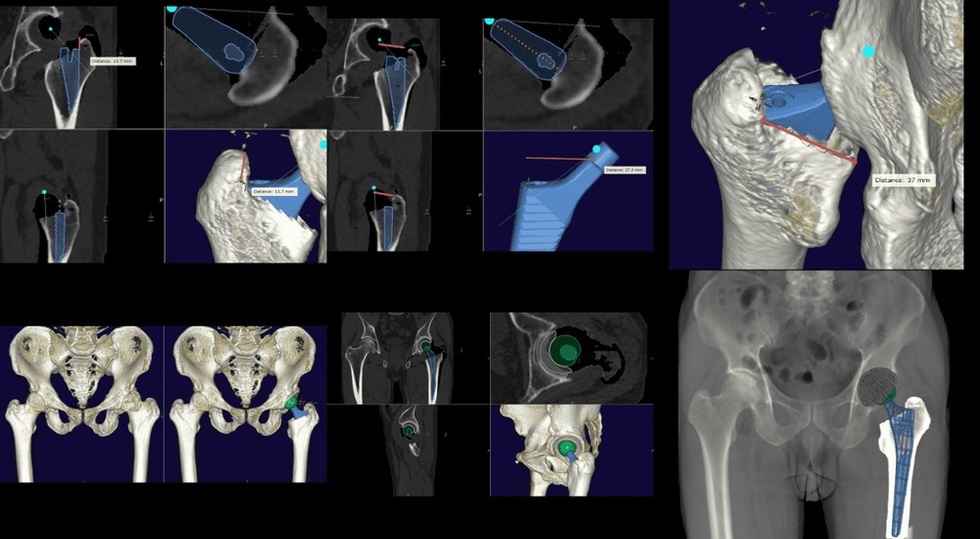

Lần đầu tiên, một bệnh nhi 12 tuổi tại Việt Nam được thay khớp háng toàn phần nhờ ứng dụng công nghệ in 3D và chế tạo mẫu cắt xương cá thể hóa (PSI).

Bệnh nhân là bé N.N.N. (12 tuổi, ở Phú Thọ), bị gãy cổ xương đùi vào năm 2024 và dù đã được phẫu thuật cố định xương, tình trạng hoại tử chỏm xương khiến cháu bé ngày càng đau đớn, dáng đi tập tễnh, cột sống vẹo nặng.

Thông thường, phẫu thuật thay khớp háng cho trẻ nhỏ là thách thức rất lớn, do hệ xương chưa phát triển hoàn thiện và nguy cơ chênh lệch chiều dài chân khi trẻ lớn lên. Trên y văn thế giới mới chỉ ghi nhận 2 ca tương tự (trẻ 10 và 11 tuổi được thay khớp háng), và đây là trường hợp đầu tiên tại Việt Nam.

Các bác sĩ Bệnh viện Vinmec (Hà Nội) đã lên kế hoạch phẫu thuật tỉ mỉ với sự hỗ trợ của mô phỏng 3D.

Nhờ chế tạo mẫu định hướng cắt xương và lựa chọn khớp nhân tạo chính xác theo kích thước xương của bé, ca mổ diễn ra thuận lợi. Sau phẫu thuật, bệnh nhi hồi phục nhanh chóng: chỉ 2 tháng sau mổ đã có thể tự đi lại bình thường, dáng người cân đối, không còn cong vẹo cột sống.

Thành công này đánh dấu một bước tiến quan trọng trong ứng dụng y học chính xác cho phẫu thuật chỉnh hình nhi khoa tại Việt Nam. Việc sử dụng công nghệ in 3D và công cụ cá thể hóa PSI đã mở ra hy vọng điều trị cho nhiều trẻ em không may bị tổn thương khớp, giúp các em có cơ hội phục hồi vận động và hòa nhập cuộc sống bình thường.